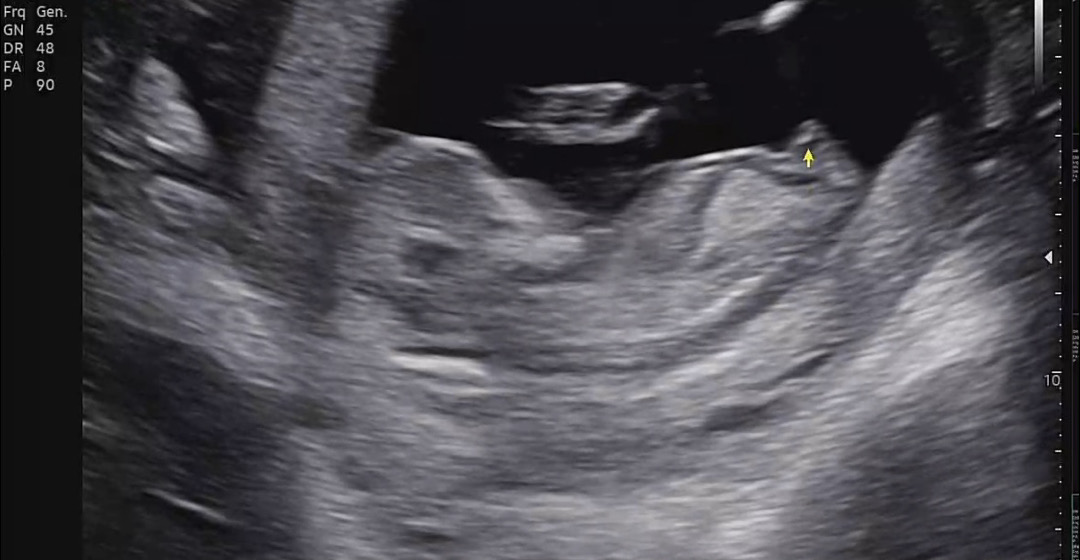

뭘까요..? 12주입니다

아들이에요!!

올라간것 같아서 아들같아요~